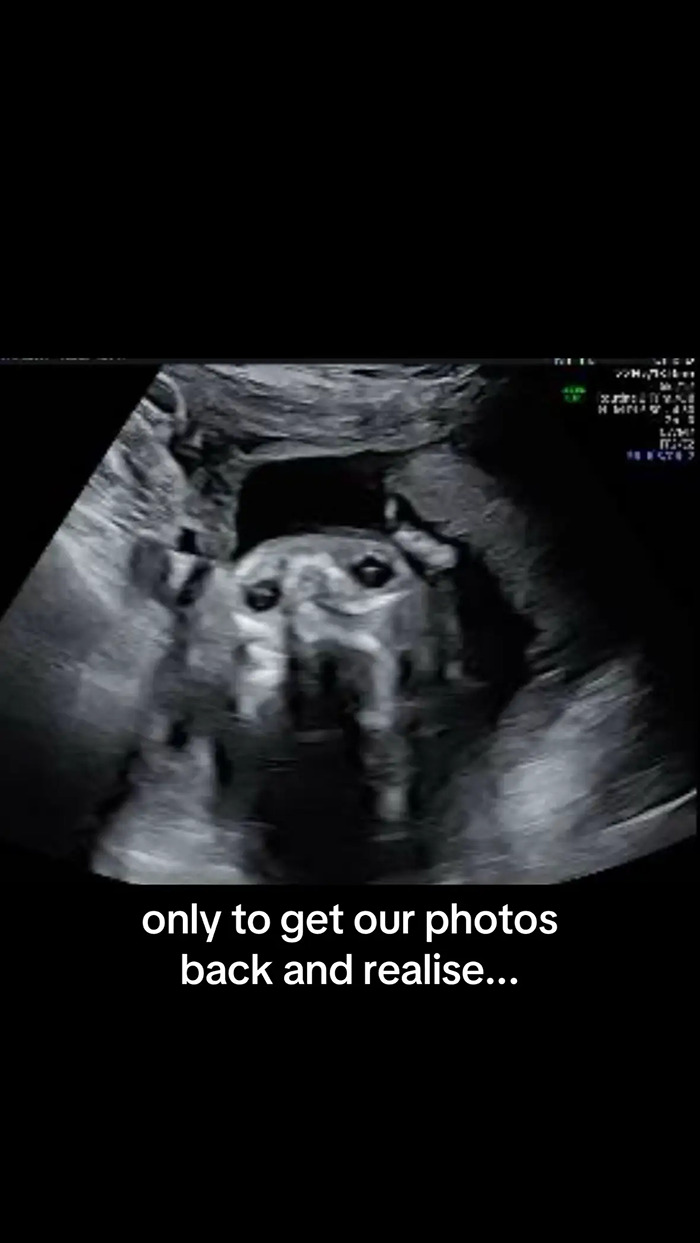

Instead of her baby, the machine showed what appeared to be the face of her dog, Goulash, staring back at her.

“We were so excited for our anatomy scan,” Egner wrote across the first slide of her post. “Only to get our photos back and realise our son looks remarkably like our dog!”

“We were skimming through them together, the three of us, as you do, admiring the little hands, the little nose… until we came across that picture and my friend goes, ‘Wait, doesn’t the baby look just like Goulash?’” she told People Magazine.

“Hard to unsee the uncanny similarity after that,” she added. “My husband and I instantly started laughing because we could see it too.”

Egner then sent the image to the rest of her family, who all saw the same thing.

“My father, unprompted, actually said the same thing,” she said. “He responded to that particular picture and said, ‘The baby looks like Goulash.’ No one can unsee it now!”